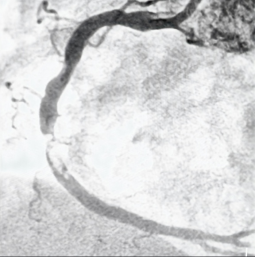

后经120送医,被确诊为“急性心肌梗死”配资网站排名第一,心脏一根主要血管几乎完全堵塞。